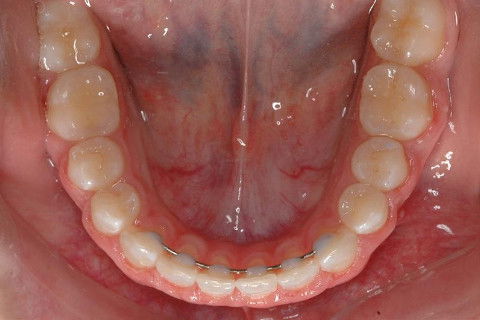

OCLUSAL INF. INICIAL.

OCLUSAL INF. FINAL